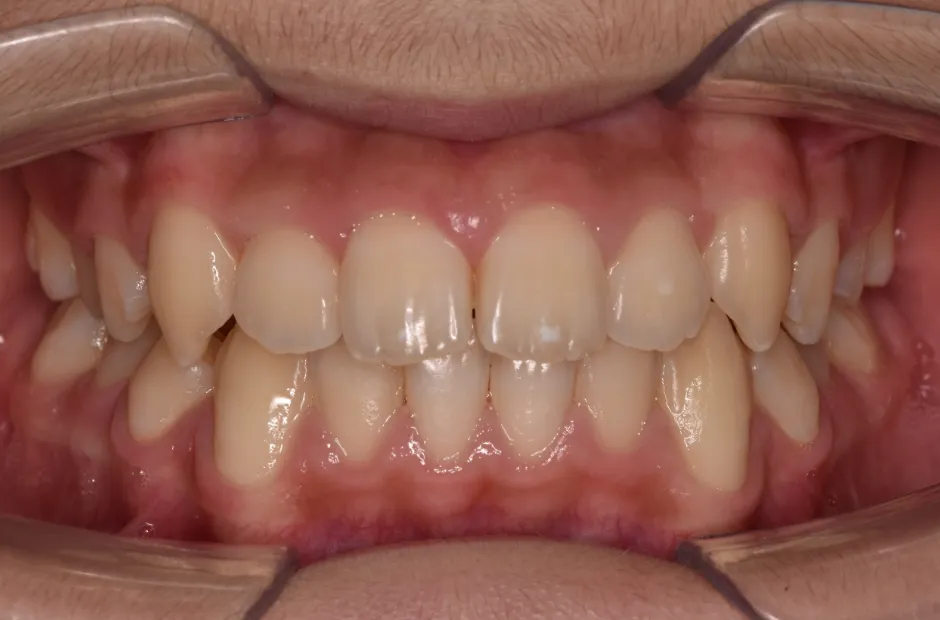

反対咬合

| 診断名・主訴 | 前歯反対咬合 |

|---|---|

| 年齢・性別 | 12歳・男性 |

| 治療期間・回数 | 1年半 18回 |

| 治療に用いた主な装置 | リンガルアーチ(前方誘導弾線) |

| 抜歯部位 | なし |

| 治療費 | 35万円(税抜) |

| リスク・副作用 | 装置による違和感・疼痛・歯肉退縮・歯根吸収・虫歯のリスクなど |

治療後

治療前

治療中